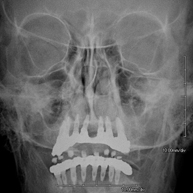

Tècnica que usa els raigs X a través de la qual s'obtenen imatges del crani per al seu estudi. Indicacions: traumatisme, tancament precoç de sutures cranials. - RX Sins Paranasals

Tècnica que usa els raigs X a través de la qual s'obtenen imatges dels sins paranasals per al seu estudi. Indicacions: dificultat respiratòria nasal, tos crònica, cefalea, mucositat - RX ATM (Articulació Temporo-Mandibular)